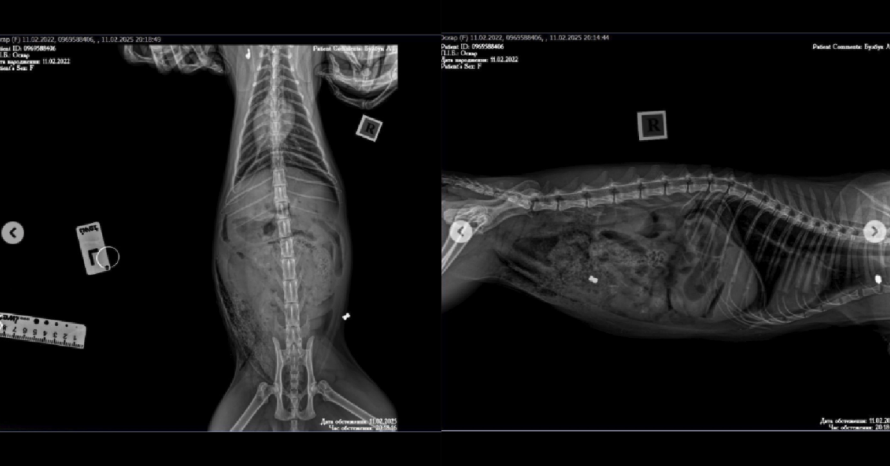

«Лікар припустив, що це кульове поранення, і воно підтвердилося. Більше того, це вже другий випадок – ще одна куля застрягла у лопатці», – розповіли власники загиблого кота.